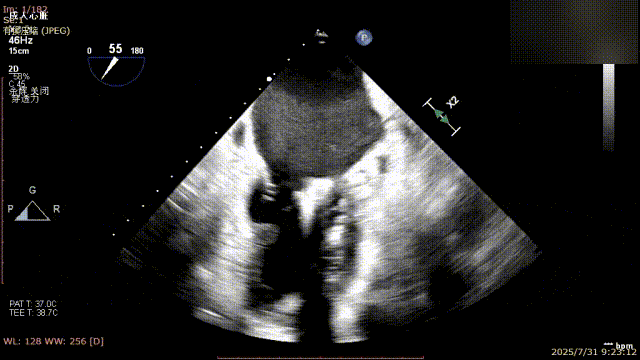

术前完善经食管超声评估,提示该患者双房大,二尖瓣重度反流4+伴后叶脱垂、后叶部分腱索断裂。根据评估结果,心脏大血管外科王安彪主任团队制定了周密的手术方案:植入一枚夹合器,钳夹P1区反流最大处,尽可能夹持全部后叶脱垂瓣叶组织,后续根据术中实时残余分流和跨瓣压差等指标,并依据实时超声监测调整治疗策略。

手术过程中,麻醉与围术期医学科副主任医师马金本确保麻醉过程平稳。心脏大血管外科主治医师董明亮穿刺股静脉置入血管鞘,并在心脏超声科梁皓主任及段福建教授TEE引导下,顺利穿刺房间隔,房间隔穿刺高度4.9cm。随后,在王安彪主任以及刘洋教授指导、心脏超声科梁皓主任TEE引导下,董明亮医师沿输送系统将延展呈“一字型”状态的国产夹合器送至左房,缓慢关闭夹合器并进行弹道测试。调整夹合器位置和方向后,董明亮医师再次将夹合器延展呈“一字型”完成跨瓣,避免发生腱索缠绕,成功捕获瓣叶后关闭夹合器,二尖瓣反流显著下降。夹合器完全解离后,超声示二尖瓣反流程度显著下降,残余反流0,平均跨瓣压差1mmHg,手术圆满成功。

解离前三维

解离后瓣叶及反流

解离后三维